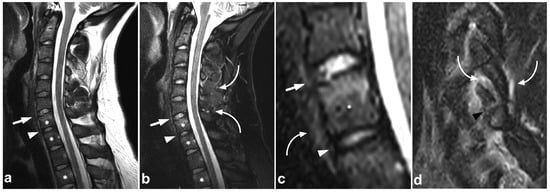

The craniocervical and atlantoaxial joints are mobile structures allowing flexion–extension movement and rotation of the head. The joints’ biomechanics and the importance of different stabilizing structures are not yet completely understood. The joint capsules, the alar ligaments, and the transverse ligaments are crucial to stability [33,38,39]. The role of the tectorial membrane is more controversial, but it might also be of importance in preventing overextension [33,40]. Injury to the stabilizing joints or ligaments may lead to instability. Isolated soft tissue injuries and avulsion fractures without complete joint dissociation (Figure 4) may occur. All the joints and ligaments mentioned above are visible on MRI. A higher field strength and dedicated proton density- and T2-weighted sequences with a smaller field of view may help to delineate these small structures better [41]. Figure 8 demonstrates a case with an upper cervical spine ligament injury.

Figure 8.

(a) Axial T2-weighted. (b) Coronal PD-weighted. (c) Right-sided off-midline sagittal PD-weighted. (d) Sagittal PD-weighted. (e) Sagittal STIR. A 12-year-old male, football injury. The right alar ligament (white arrows) is torn. The right side of the transversal ligament is thickened and heterogenous, suggesting a partial distension injury (white arrowheads). The left alar ligament (black arrows) and the central and left-sided portions of the transversal ligament (black arrowheads) are intact. The tectorial membrane is unharmed (curved black arrows), but the apical ligament of the dens is poorly visible, probably torn (curved white arrow). Apparent asymmetry of the lateral atlantodental intervals is seen, but there are no signs of occipitocervical or atlantoaxial joint capsule disruption.